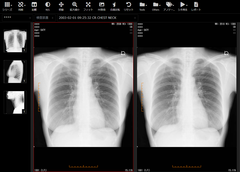

ビューア画面2

3. Webブラウザで動作する高速なビューア

ビューアはWebブラウザ(Google ChromeやFirefox)上で動作するので、クライアント端末に新たにソフトウェアをインストールする必要がありません。ネットワーク内のどの端末からでも、WebブラウザからURLにアクセスしてログインするだけで画像を閲覧できます。CTやPETなどの大量の画像が含まれる検査もスピーディに表示することができます。